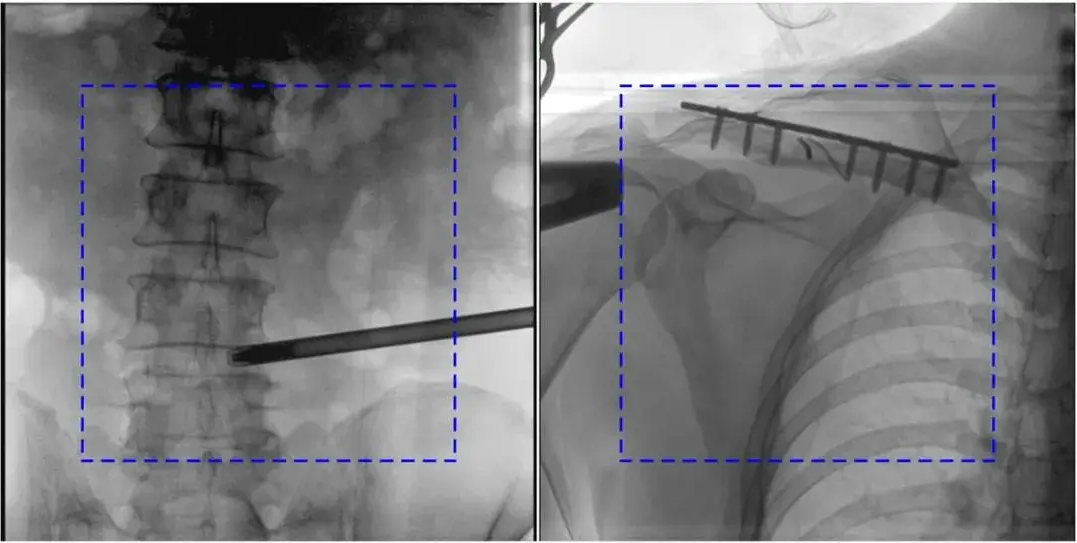

2. 自动曝光控制(AEC)异常

AEC模式下,金属植入物或患者体位偏离视野中心可能导致曝光不足或过度。

解决办法:手动调整曝光参数,确保感兴趣区域位于视野中央;避免金属干扰,必要时调整患者体位。